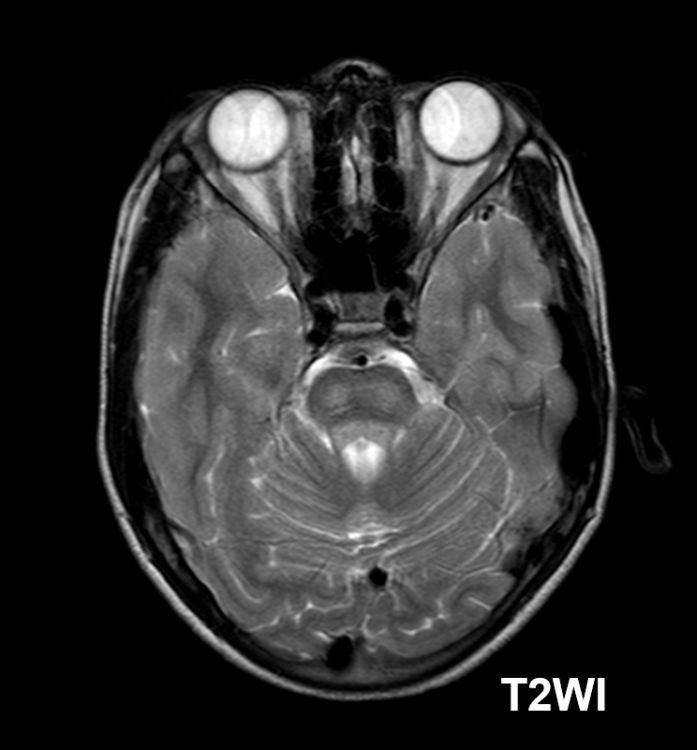

#AJNRcc >> November 20, 2023 >> What is the diagnosis for this 77-year-old woman with atrial fibrillation who presents with altered mental status after undergoing catheter ablation? Submit your answer at ow.ly/ctXf50Qcy4z